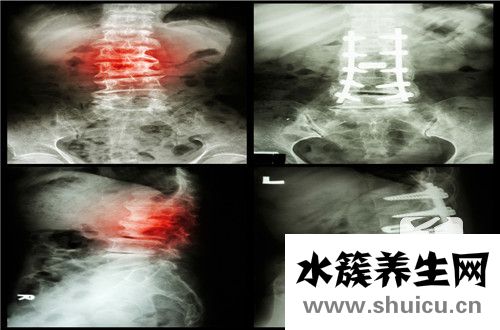

脊柱是我們頸部橫穿背部的一段,可以說是背部的脊柱。我們可以根據(jù)脊柱左右徑的大小來區(qū)分是否狹窄。一般的判斷依據(jù)是小于13mm就比較窄,小于10mm就肯定窄。進行手術(shù)醫(yī)療時,我們需要固定螺釘。所以如...